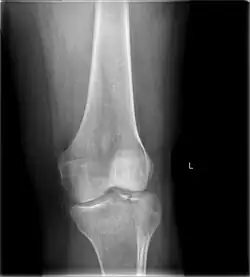

Tibial plateau fracture

A tibial plateau fracture is a break of the upper part of the tibia (shinbone) that involves the knee joint.[1] This could involve the medial, lateral, central, or bicondylar (medial and lateral).[3] Symptoms include pain, swelling, and a decreased ability to move the knee.[1] People are generally unable to walk.[2] Complication may include injury to the artery or nerve, arthritis, and compartment syndrome.[1]